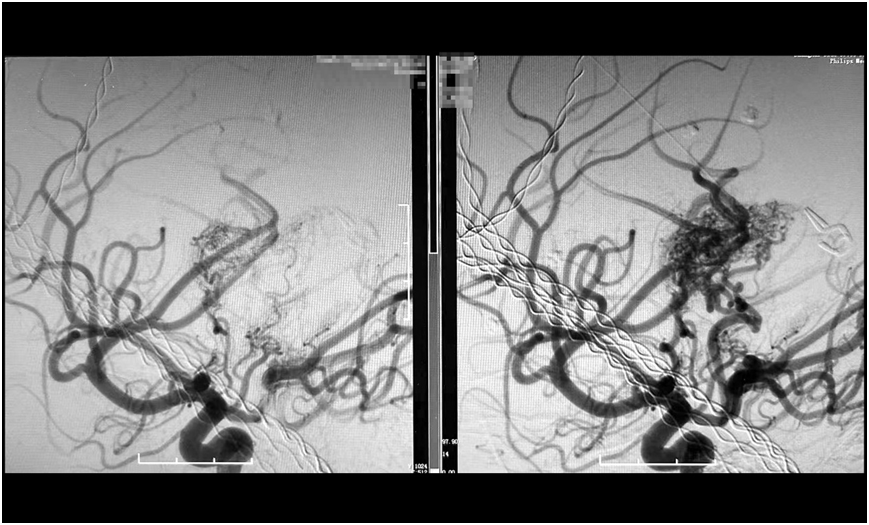

image.png

巨大腦動靜脈畸形(右),被順利栓塞(左)

經過數小時的精雕細琢,手術團隊成功栓塞預期目標責任血管。術后造影顯示,假性動脈瘤已完全消失,畸形血管團達到預期栓塞效果,所有正常血管血流保持通暢(mTICI 3級)。